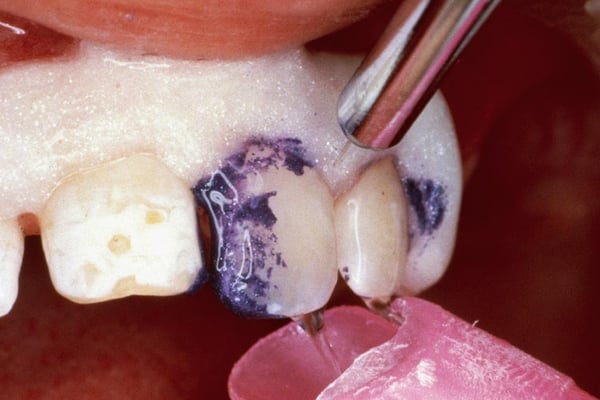

Trước và sau khi điều trị vi mài mòn với Opalustre

- Bảo vệ mô mềm là rất quan trọng, sử dụng đê cao su, và nếu muốn có thể sử dụng đê cao su kết hợp thêm chất cách li quang trùng hợp ở viền nướu.

- Bắt đầu với 2 đến 3 răng một lúc, lời khuyên là nên đặt một lớp Opalustre khoảng 1mm trên vùng răng bị đổi màu và sử dụng cùng đài đánh bóng cao su. Dùng áp lực trung bình đến mạnh khoảng 500 vòng/phút trong thời gian 60 giây.